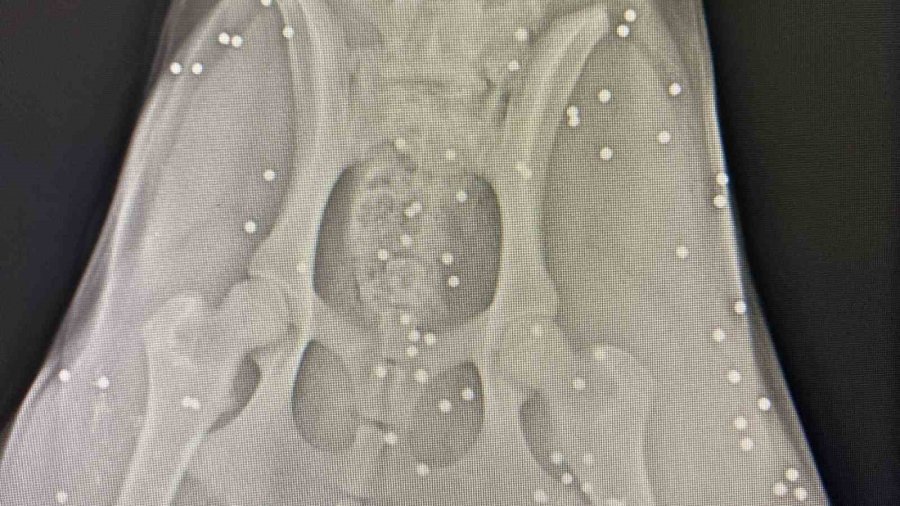

Antalya'nın Aksu ilçesinde silahla vurulan sokak köpeğinin çekilen röntgen görüntüsü adeta şoke etti. Yapılan incelemede köpeğin kalçasında onlarca saçmaya rastlanırken, veterinerde ilk müdahalesi yapılan köpek, bir hayvansever tarafından bakımı üstlenildi.

Polis ekipleri ise şikayet üzerine harekete geçerek olayla ilgili inceleme başlattı. Köpeğin durumu hakkına açıklama yapan Veteriner Mustafa Gülcü, "Köpek bize silahla yaralanma şikayetiyle geldi. Biz hemen ilk müdahalesini yaptık. Ardından röntgen çektik, incelediğimizde çok sayıda saçmaya rastladık. Yakın mesafeden sıkılsa sinirlerine zarar verebilirdi" sözlerine yer verdi.

"Röntgen görüntülerine baktığımızda köpeğin arka kısmı tamamen yok"

Yaşananları anlatan Gülhan Tünay, "Sabah saatleriydi iki el silah sesi duydum. Ardından köpeği acı içerisinde buldum. Eşime seslenerek eyvah köpeği vurdular dedim. Köpek arka tarafı kanlar içinde geldi. Seçim gecesi de bir köpek vurulmuştu, o köpek şuan ampute oldu. Veterinere söyledim gelip aldılar. Daha sonra polisi aradım ve köpeği vuran kişiden şikâyetçi oldum. Röntgen görüntülerine baktığımızda köpeğin arka kısmı tamamen yok. Kaç tane saçma olduğunu bilmek zor. Şuan durumu çok iyi değil, ilk getirdiğimizde hayati tehlikesi vardı. Şuan serum takılı biz de bekliyoruz. İnşallah özürlü kalmaz. Ne hissettiğini bilmiyorum. İnsanların artık silahlanması önlensin istiyorum" dedi.